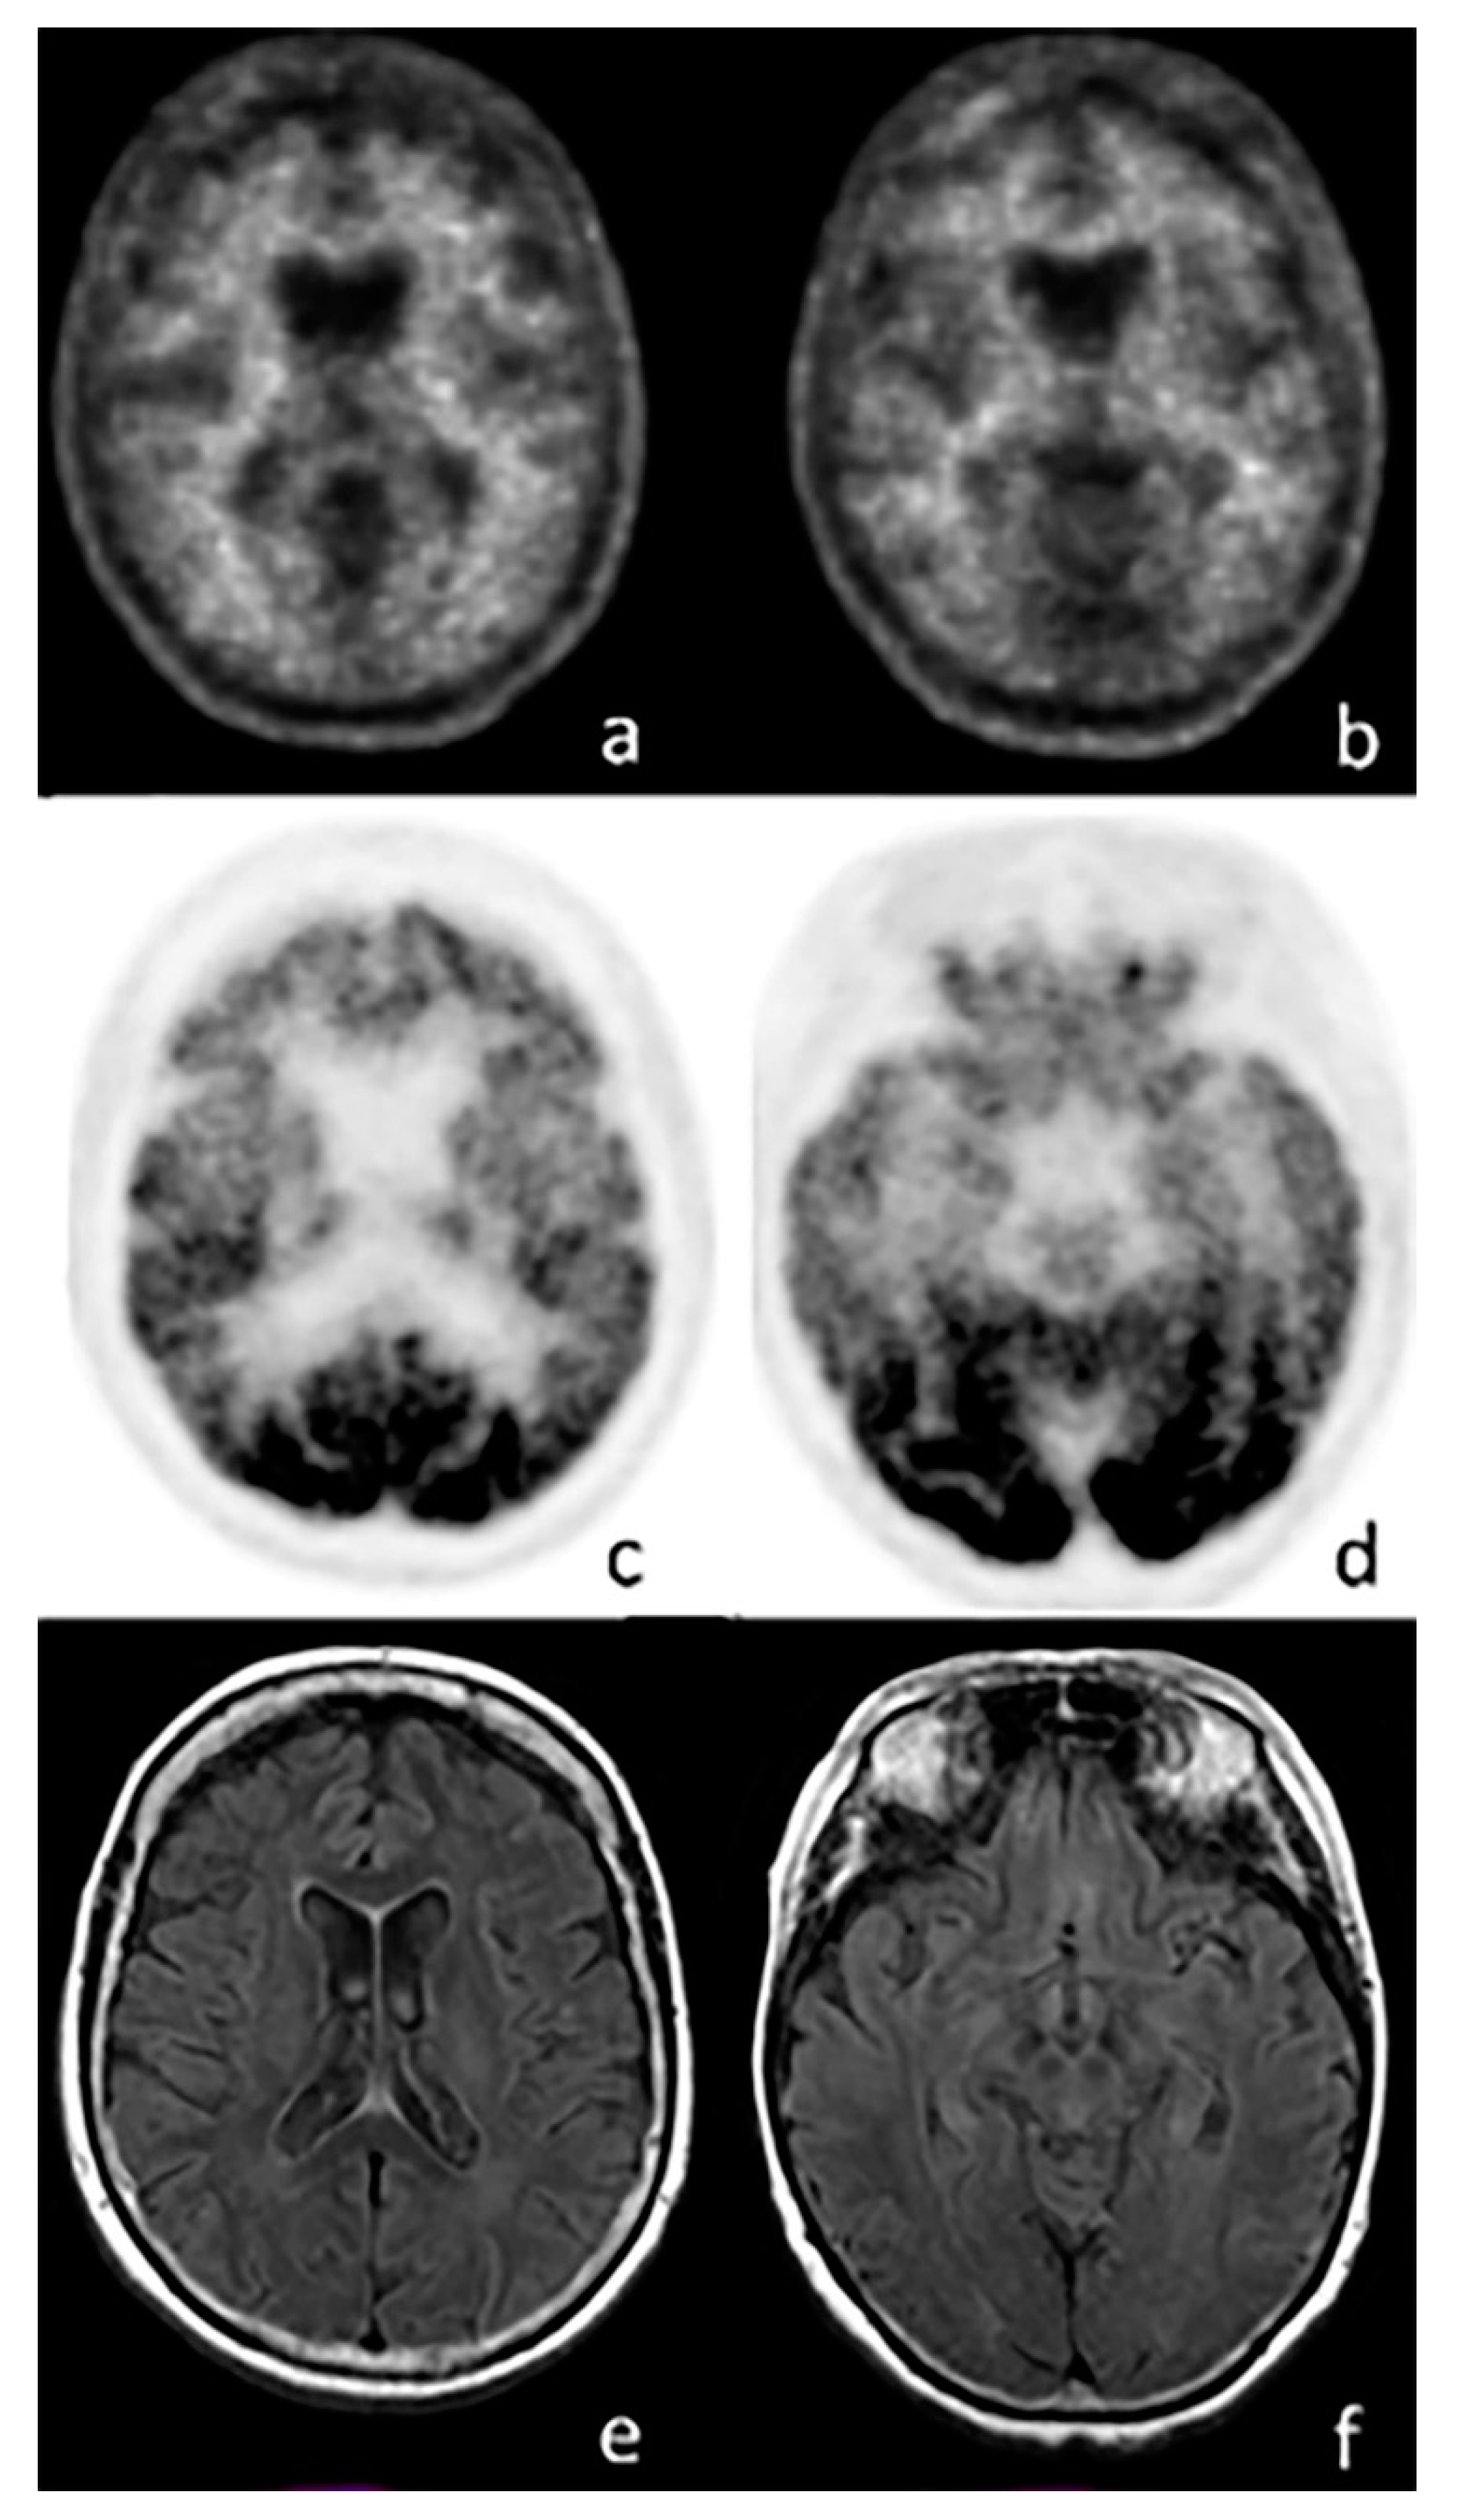

3.1. FDG-PET in FTD

4.3. FDG-PET Imaging in SNCApathies

5.1. FDG-PET Imaging in Atypical Parkinsonian Syndromes